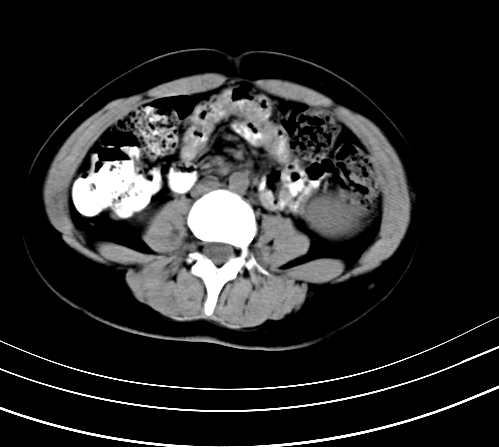

延时5分钟

延时10分钟